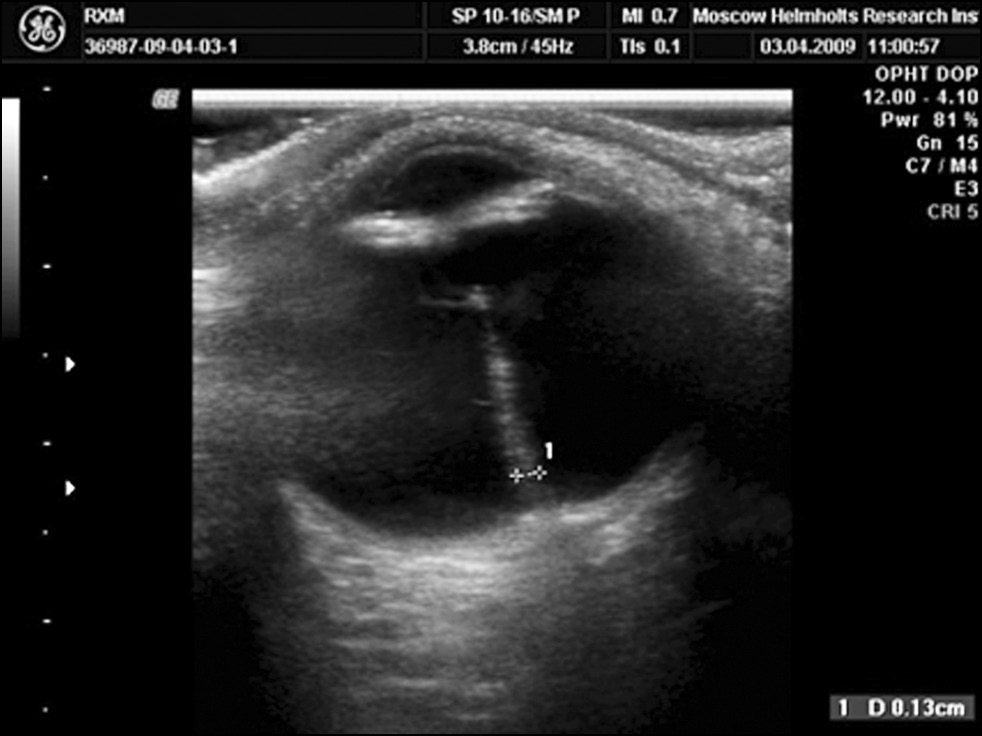

Group 1 (32 eyes) included children with the least pronounced manifestations of PHPV. The anteroposterior axis (APA) of the eye corresponded to the age norm or was slightly reduced by 0.5–0.8 mm (21 eyes). Ultrasound examination (B-scan and Dopplerography) showed a thin strand up to 1.0 mm in diameter in the depleted hyaloid artery, running from the OND to the posterior capsule of the lens or breaking off at different distances from the OND (Fig. 1).

Fig. 1. The weight of the neglected hyaloid artery running from the optic nerve disc to the posterior capsule of the lens. B-scan.